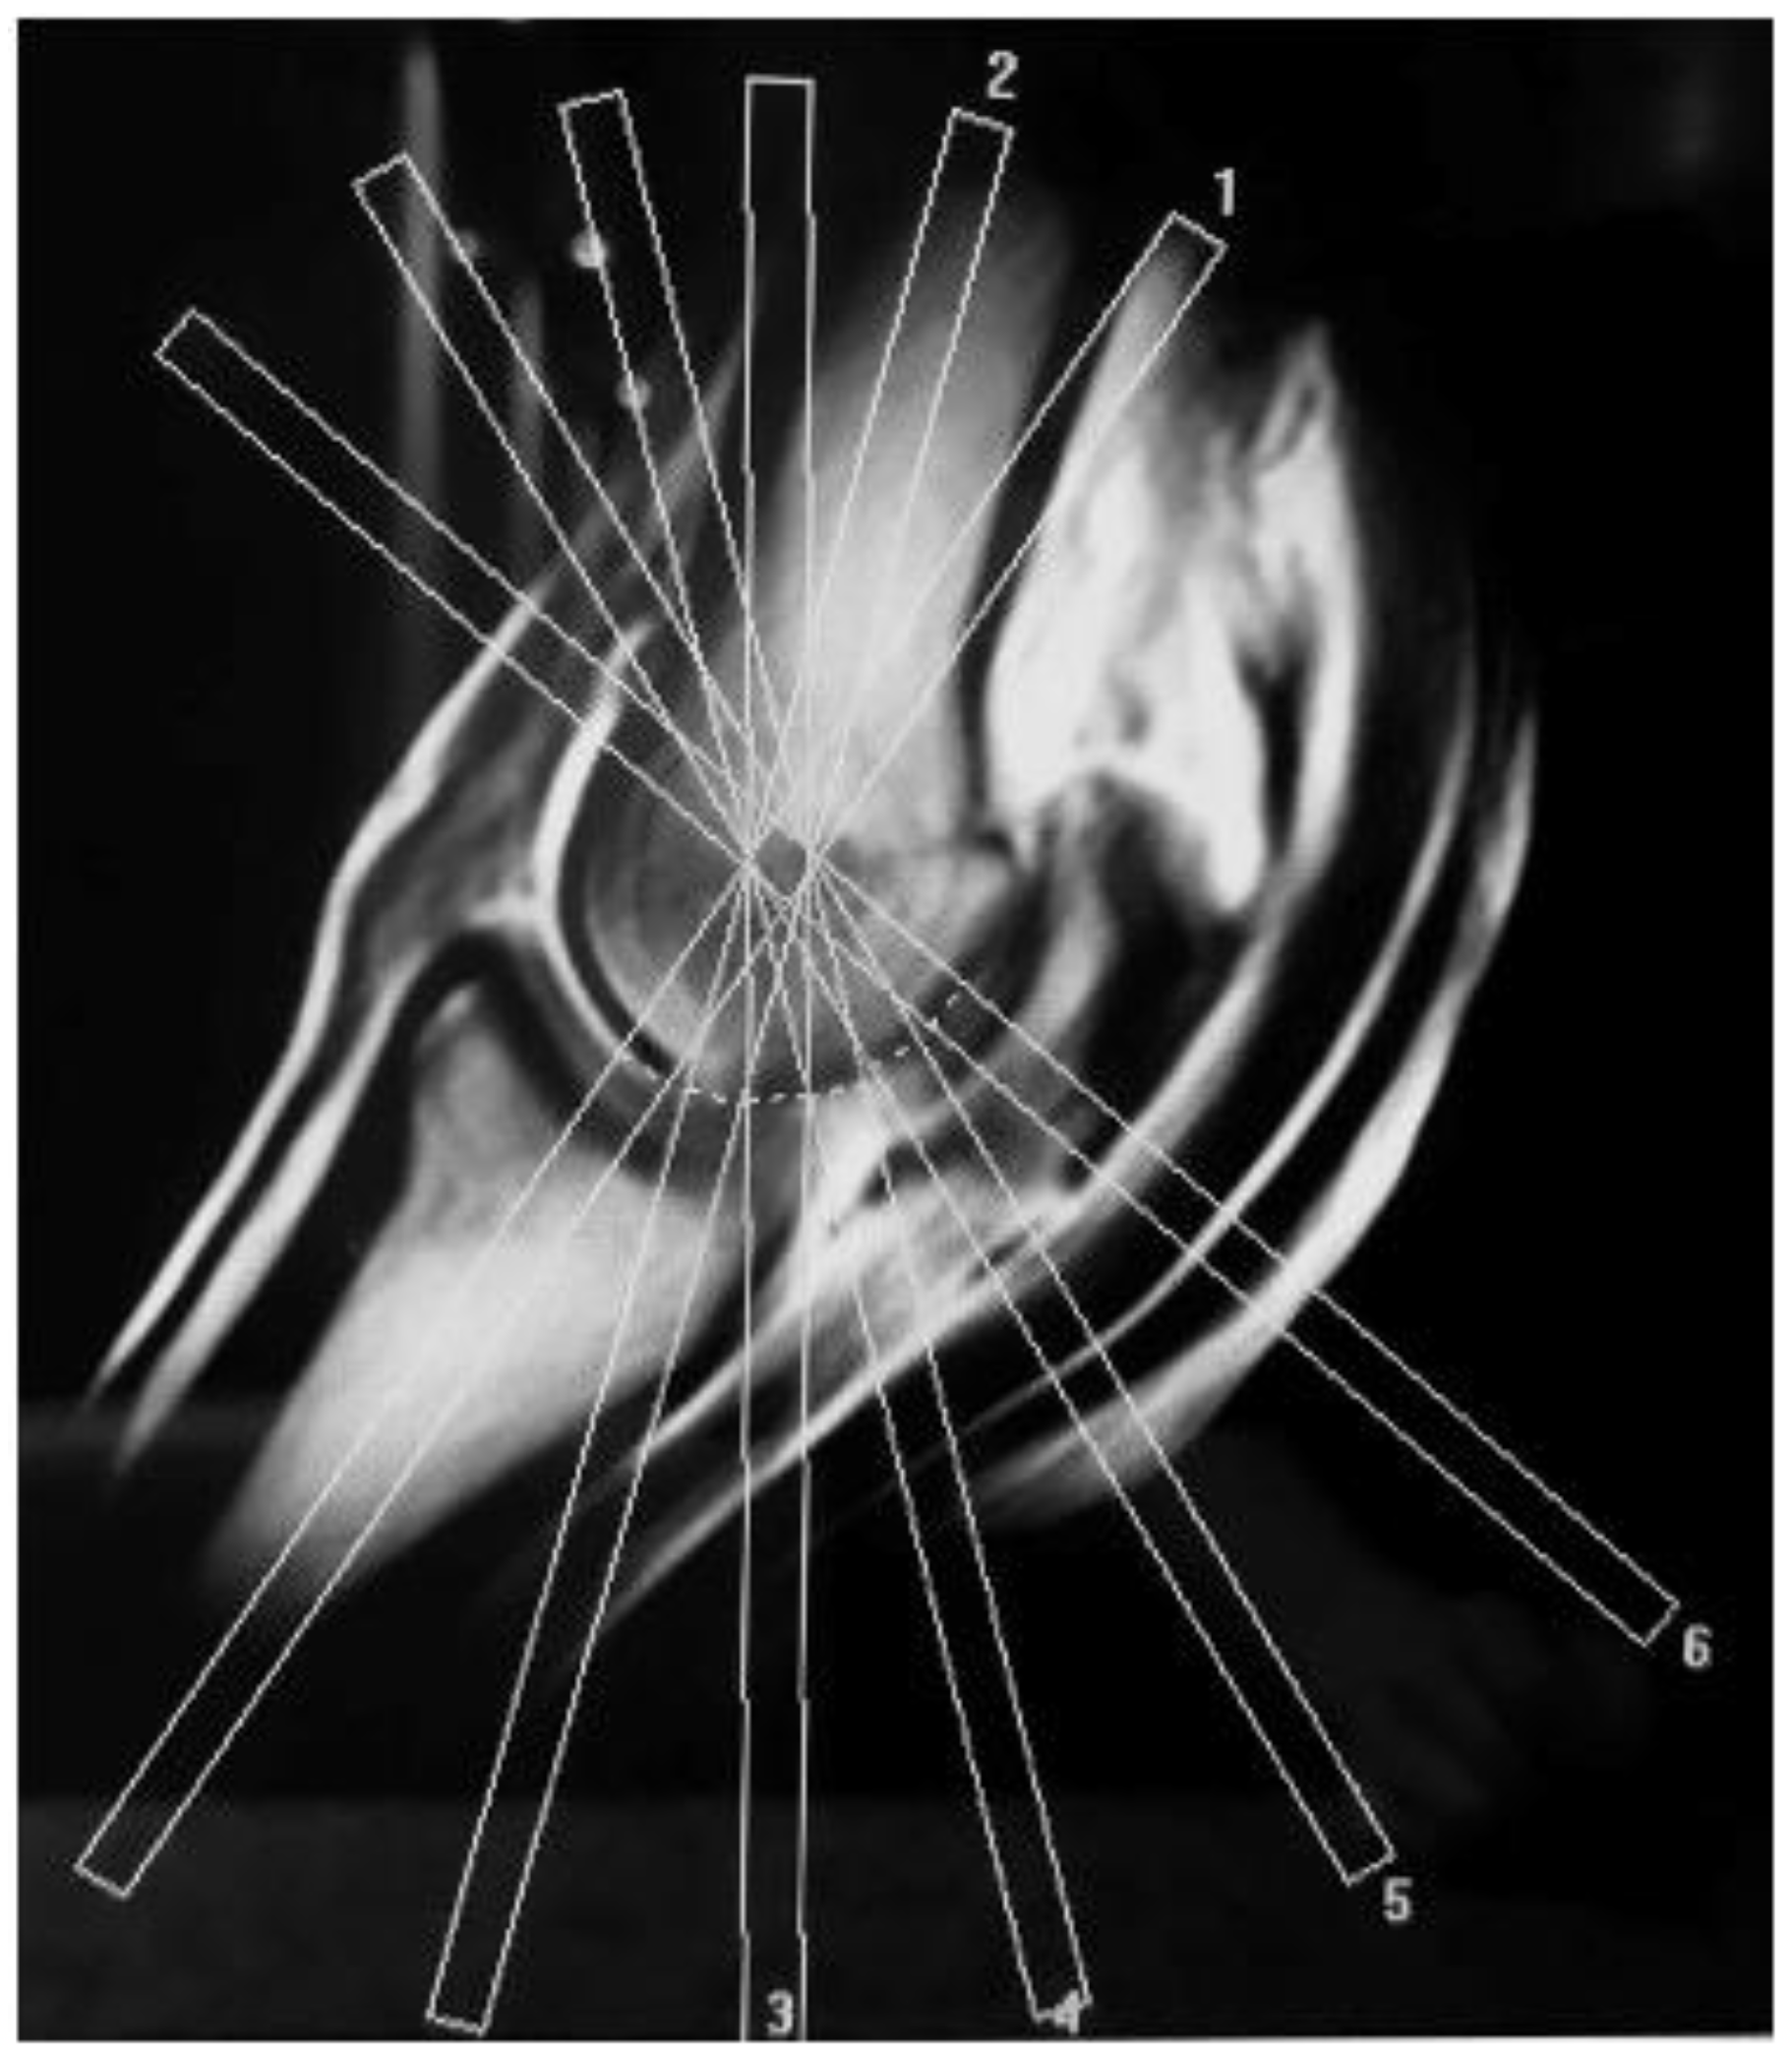

2. Materials and Methods